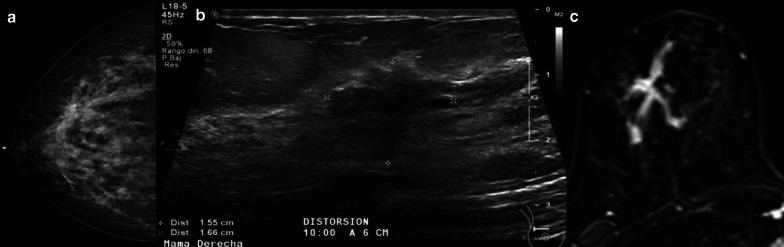

Breast lesions with uncertain malignant behavior, also known as high-risk or B3 lesions, are composed of a variety of pathologies with differing risks of associated malignancy. While open excision was previously preferred to manage all high-risk lesions, tailored management has been increasingly favored to reduce overtreatment and spare patients from unnecessary anxiety or high healthcare costs associated with surgical excision. The purpose of this work is to provide the reader with an accurate overview focused on the main high-risk lesions of the breast: atypical intraductal epithelial proliferation (atypical ductal hyperplasia), lobular neoplasia (including the subcategories lobular carcinoma in situ and atypical lobular hyperplasia), flat epithelial atypia, radial scar and papillary lesions, and phyllodes tumor. Beyond merely presenting the radiological aspects of these lesions and the recent literature, information about their potential upgrade rates is discussed in order to provide a useful guide for appropriate clinical management while avoiding the risks of unnecessary surgical intervention (overtreatment).

具有不确定恶性行为的乳腺病变,也称为高危或B3病变,由多种具有不同相关恶性风险的病理类型组成。虽然以前首选开放切除来处理所有高危病变,但为了减少过度治疗并使患者免受与手术切除相关的不必要焦虑或高昂医疗费用,针对性管理越来越受到青睐。这项工作的目的是为读者提供一个准确的概述,重点关注乳腺的主要高危病变:非典型导管上皮增生(非典型导管增生)、小叶肿瘤(包括小叶原位癌和非典型小叶增生亚类)、扁平上皮异型增生、放射状瘢痕和乳头状病变,以及叶状肿瘤。除了仅仅呈现这些病变的放射学特征和近期文献外,还讨论了它们的潜在升级率信息,以便为适当的临床管理提供有用的指导,同时避免不必要手术干预(过度治疗)的风险。